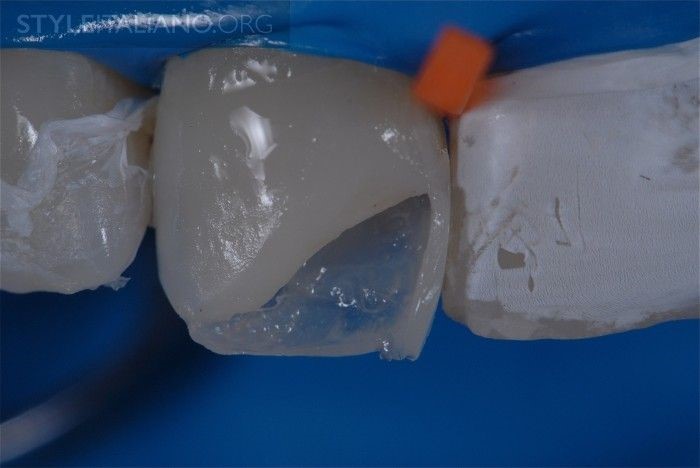

Hình 20. Tip 3. Sau khi lấy bỏ phần composite màu ngà thừa, không nên để bề mặt composite ghồ ghề lởm chởm khi đắp tiếp lớp composite màu men. Tác giả gợi ý sử dụng chổi (cọ) trám phù hợp để vuốt láng phần composite và đẩy composite màu ngà thêm về phía men răng để tạo sự chuyển tiếp. Nhờ đó sẽ giảm sự khác biệt đột ngột về màu sắc giữa miếng trám và mô răng thật.

Hình 21. Khắc tạo hình các thùy trên rìa cắn răng cửa ở lớp composite màu ngà để tái tạo thẩm mỹ tự nhiên cho răng sau trám.